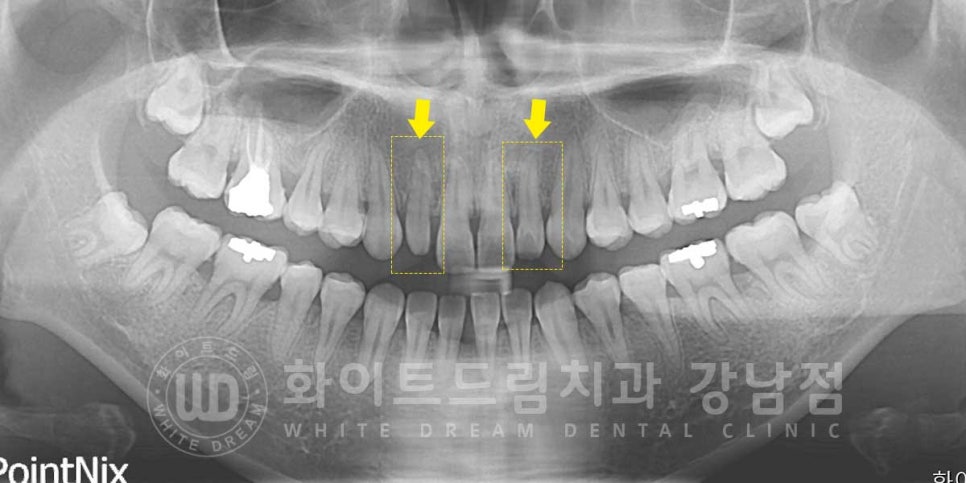

왜소치는 보통 큰 앞니 옆 치아, 측절치에 많이 발생하는데요.

환자분의 초진 구내 사진을 보면

옆 측절치들이 앞니에 비해 크기가 작아 앞니가 더욱 부각되어

토끼 앞니처럼 보이는 것이 확인됩니다.

일반적으로 크게 작지 않은 왜소치는 라미네이트로 치료를 많이 진행하지만

이렇게 치아 모양이 크게 작은 경우는 크라운을 이용하여 치료를 진행합니다.

왜소치 올 세라믹 크라운 치료를 하는 이유는?

치아의 모양이 너무 작고 빈 공간이 넓으면 라미네이트를 부착해도

금방 떨어질 위험이 크기 때문입니다.